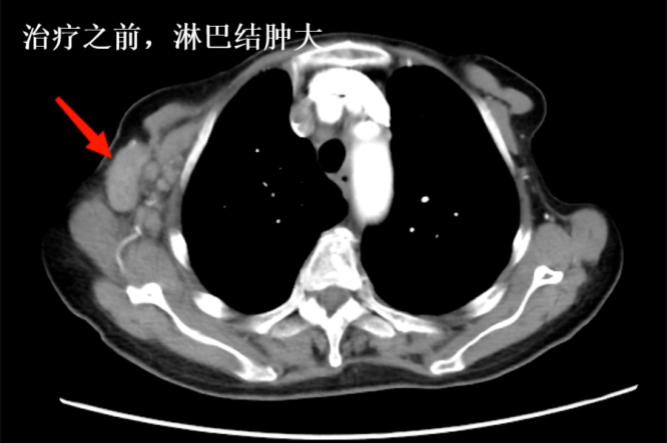

王奶奶在治療后,并沒有出現(xiàn)任何不適的癥狀。更令人驚喜的是,當(dāng)她入院復(fù)查時(shí),發(fā)現(xiàn)腫瘤竟然比之前縮小了。這個(gè)顯著的療效讓王奶奶和家屬對(duì)抗腫瘤的信心一下子足了起來。